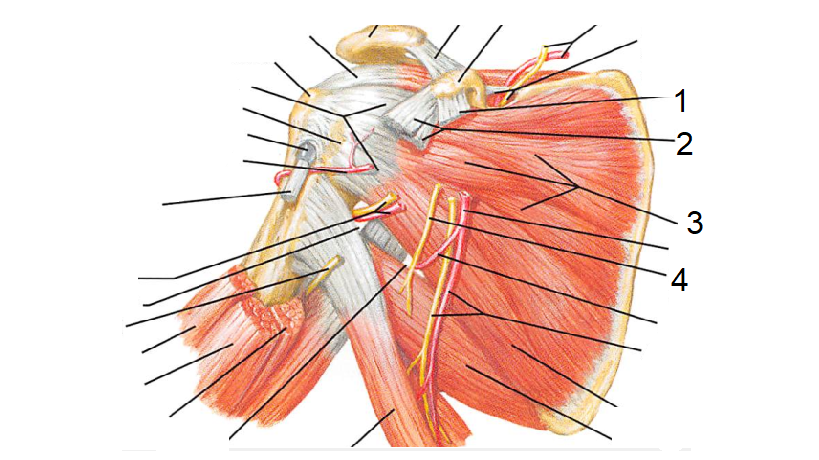

14

1 - M. romboide menor

2 - M. infraespinhal

3 - M. redondo menor

4 - M. latissimo do dorso